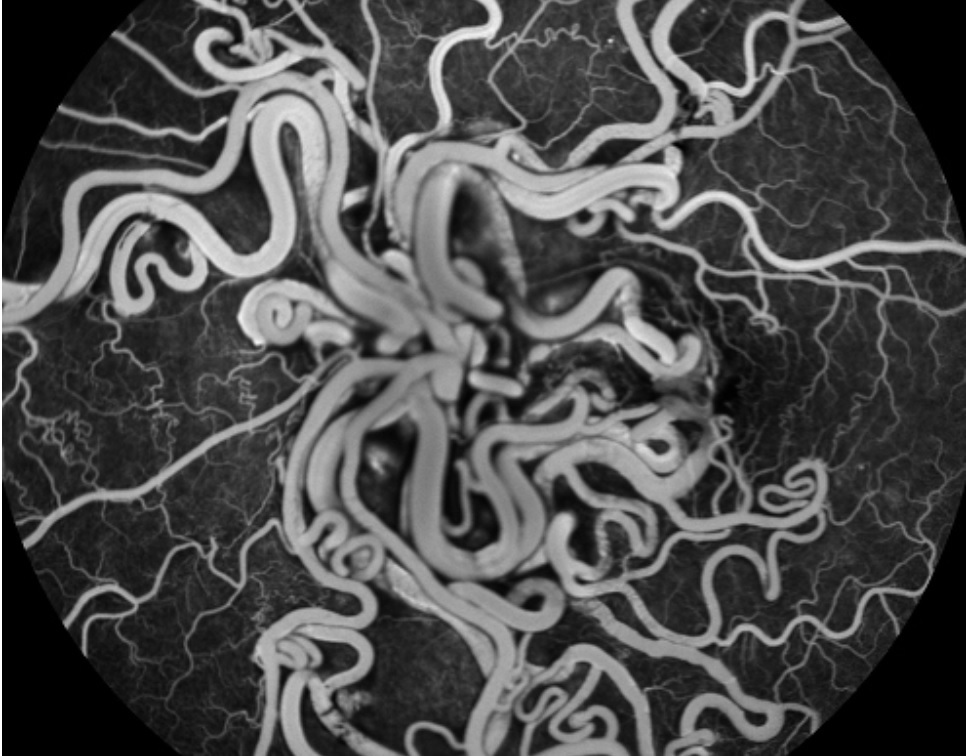

Quais são as principais alterações oftalmológicas do Hemangioma Racemoso?

Unilateral

BAV em 80% dos casos

Anastomoses arteriovenosas sem capilares interpostos

Aumento do calibre vascular (A. e V. com calibre similar)

Qual é o padrão do Hemangioma Racemoso no exam de Angiografia com Fluoresceína?

Não há extravasamento vascular

O que é a Síndrome de Wyburn-Mason?

Doença sistêmica que cursa com Hemangioma Racemoso e má-formação arteriovenosa ipsilateral em SNC